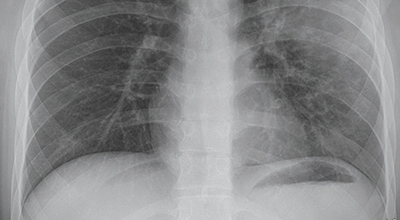

초기에 가벼운 기침으로 시작해 호흡하는 것조차 힘들어지게 되는데요 폐에 발생한 염증으로 인해서 폐의 신전성이 감소하고, 폐를 구성하는 폐포 세포가 망가져 적정 수준의 산소를 보관하지 못하기 때문에 호흡곤란이 유발될 수 있어요.

폐렴과 독감과 감기의 차이

기침, 발열, 오한등으로 초기증상은 모두 비슷하지만 차이점이 있으므로 이 점을 잘 체크하셔야 합니다

감기 : 2~3일간 미열 콧물, 코막힘. 인후통

독감 : 갑작스러운 증상 악화 39도 이상의 고열 발생

폐렴 : 누런 가래, 호흡곤란, 흉통 독감보다 증상이 오래 발생